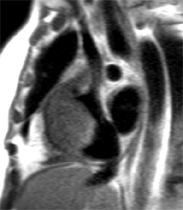

Envahissement tumoral de la paroi latérale du VG avec hypersignal T2 (séquence STIR) et hypersignal post-gadolinium (PSIR) chez un patient de 49 ans aux antécédents de séminome une quinzaine d’année auparavant avec récidive l’année précédente, traitée par chimiothérapie et extension sous forme de nodules pulmonaires et de métastase cérébrale traitée par radiothérapie. La paroi latérale infiltrée est hypokinétique avec FEVG abaissée à 54%.